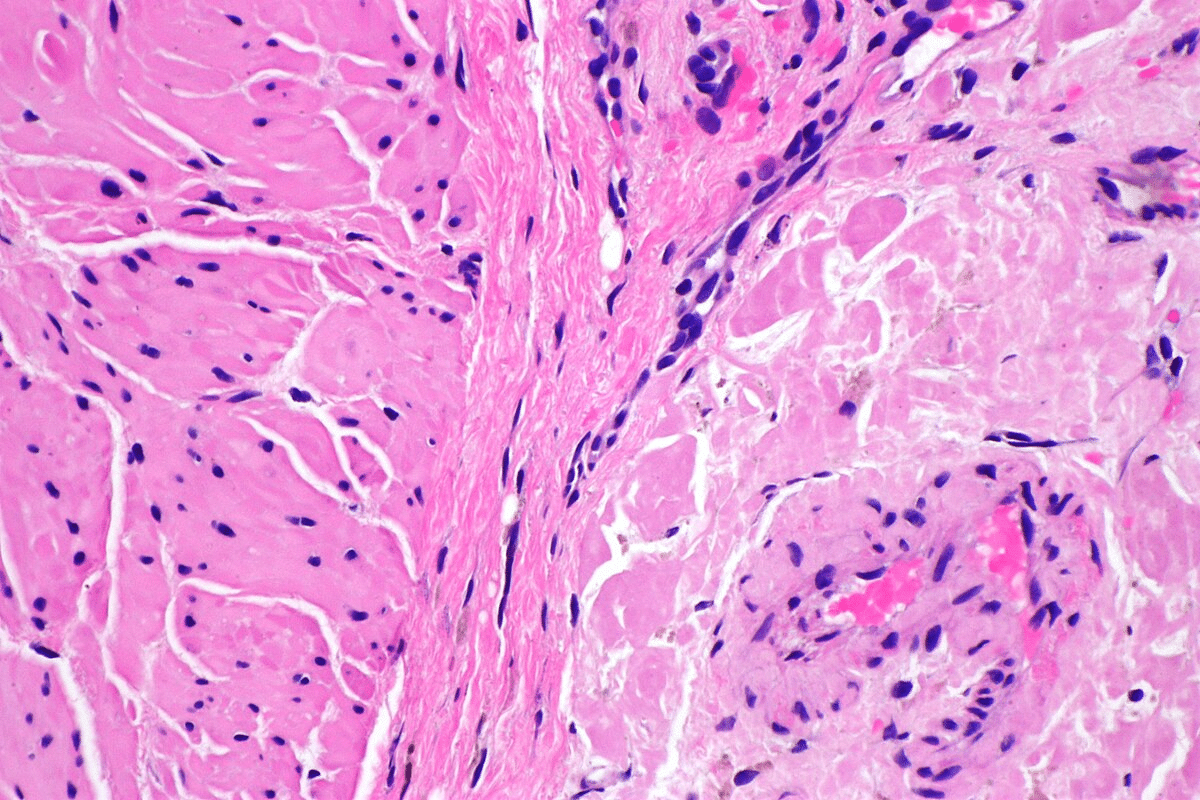

Diagnostic Approaches and Challenges

Diagnosing amyloidosis involves several steps, including clinical evaluation, lab tests, and sometimes biopsy. The main challenge is identifying the type of amyloidosis and how much it affects organs.

Advanced tests like mass spectrometry and genetic testing have made diagnosing amyloidosis more accurate. But, its rarity and nonspecific symptoms often cause delays in diagnosis. This highlights the need for healthcare providers to be more aware of amyloidosis.